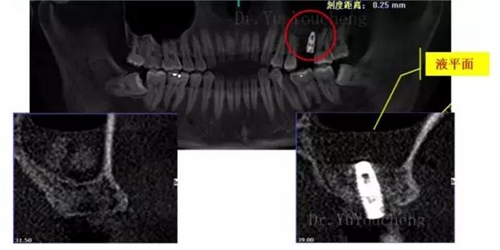

系列課開播前小編為大家預(yù)告了一例上頜竇外提升術(shù)后種植體方向改變的病例,當(dāng)時頓生種種疑惑:“真的么?怎么會?怎么辦!!”在本次課程中余教授給出了答案:上頜竇外提升同期種植有一重要的因素,即種植體初期穩(wěn)定性的獲得。該患者由于其骨量的嚴(yán)重不足,雖然可通過大直徑覆蓋螺絲保證種植體不至于滑落,但隨著竇粘膜的運(yùn)動和部分移植骨的吸收,種植體方向最終受到了影響,這也提示我們在制定治療計劃過程中應(yīng)慎重考慮這一因素,以確保更好的種植預(yù)后效果。